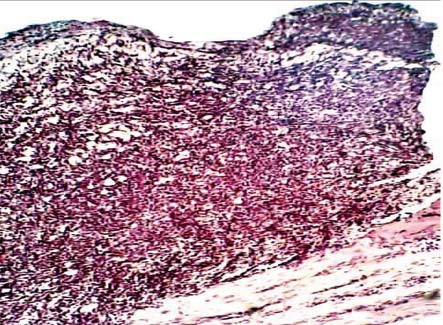

У животных, получавших лечение диметилселенитом и диметилсульфоксидом, на 2-е сутки наблюдения морфологическая картина была схожей с контрольной группой в эти же сроки. Однако уже на 4-е сут у крыс 1-й группы лейкоцитарная инфильтрация в краях раны отсутствовала, раневая поверхность была представлена широким слоем молодой грануляционной ткани с множеством мелких новообразованных капилляров. Элементы грануляционной ткани с признаками созревания проникли и между пучками мышечных волокон. Отмечалось наличие коллагеновых волокон, окруженных большим количеством полибластов, макрофагов, эпителиоидных клеток с тенденцией их трансформации в фибробласты (рис. 1).

Рис. 1. Морфологическая картина раны при лечении диметилселенитом на 4-е сут от начала наблюдения. Хорошо видны многочисленные полнокровные капилляры, коллагеновые волокна, окруженные эпителиоидными клетками с тенденцией трансформации в фибробласты. Окраска гематоксилин-эозином, ок. х7, об. х20